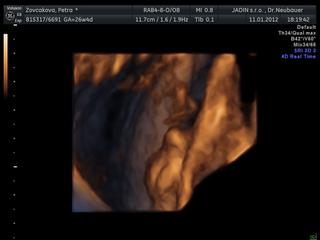

nechodim tu casto, takze nestiham to vsetko sledovat. Urcite mi kopa veci usla, chcela by som sa spytat, kde v Ba robia 4D, kedze vy uz svoje krasne obrazky mate a za kolko. Na nete som sa akosi k cene nedopatrala. Viem len tolko, ze na 4D je teraz ten najvhodnejsi cas. Dakujem